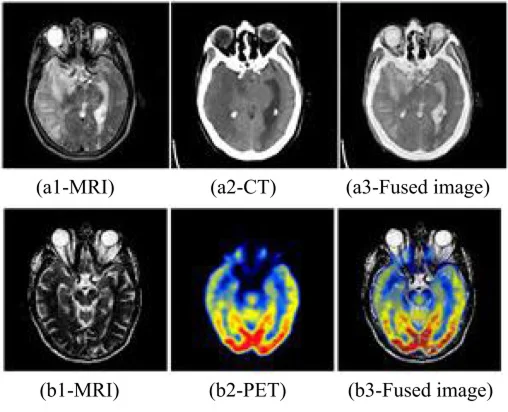

Medical imaging analysis involves processing and interpreting images generated using equipment such as MRI, CT scan, X-ray, and ultrasound. Traditionally, this was a manual, time-intensive process prone to variability and human error. However, AI-driven methods are transforming this domain by automating image interpretation with precision and speed.

Medical image segmentation refers to the process of partitioning an image into meaningful regions, such as identifying organs, tumors, or lesions. This step is crucial because it enables AI models to focus on relevant structures, improving disease detection and treatment planning.